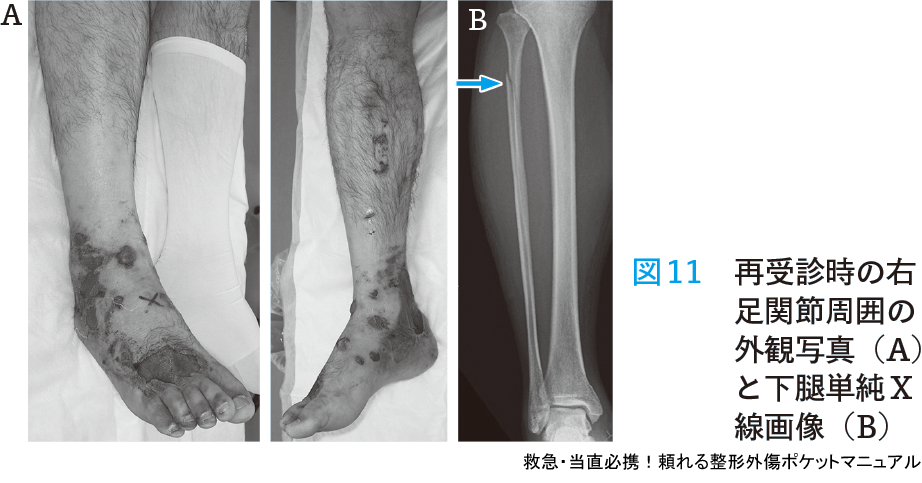

- 所見と経過:右足関節に腫脹があり,同部位の疼痛と圧痛もあった.単純X線では脛骨遠位部骨折(後果骨折)があったため(図10)下腿シーネ固定を行い,後日整形外科外来受診を指示した.荷重制限については指示しておらず,帰宅後は患肢荷重を行っていた.6日後に整形外科外来を受診したが,右足関節骨折および腓骨近位部骨折の診断となり(図11),緊急で創外固定手術を行った.

診察時は脛骨遠位部骨折のみと診断し,転位も小さいため外固定のみ行い荷重制限を指示せず帰宅させてしまい,軟部組織の状態が悪化してしまった.本症例は腓骨近位部骨折を合併した不安定性が大きい骨折型であったため,軟部組織保護のため入院安静加療が望ましい症例である.

疼痛部位をしっかり確認し,骨折の見逃しがないかを注意深く観察することが重要である.また,足関節骨折は下腿骨幹部に損傷が及ぶこともあることを知っておく必要がある.